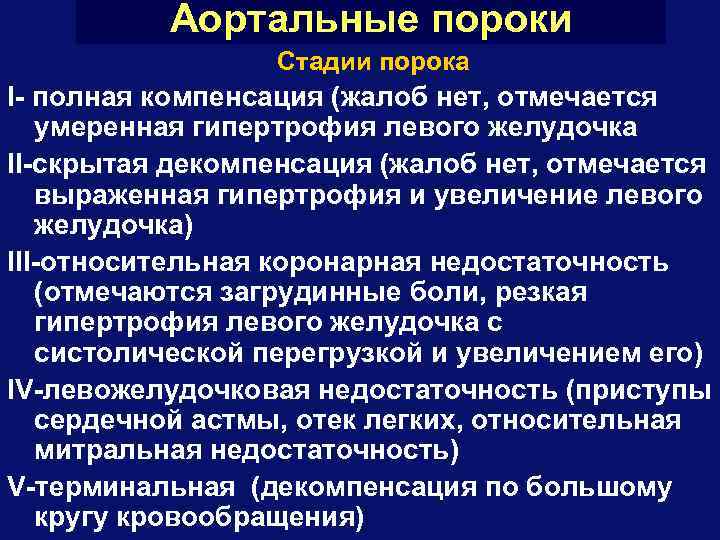

Аортальные пороки Группы порока I- преобладание стеноза: а) с нормальной или расширенной аортой б) с узкой аортой II-преобладание недостаточности: а) с нормальной или расширенной аортой б) с узкой аортой

Аортальные пороки Стадии порока I- полная компенсация (жалоб нет, отмечается умеренная гипертрофия левого желудочка II-скрытая декомпенсация (жалоб нет, отмечается выраженная гипертрофия и увеличение левого желудочка) III-относительная коронарная недостаточность (отмечаются загрудинные боли, резкая гипертрофия левого желудочка с систолической перегрузкой и увеличением его) IV-левожелудочковая недостаточность (приступы сердечной астмы, отек легких, относительная митральная недостаточность) V-терминальная (декомпенсация по большому кругу кровообращения)